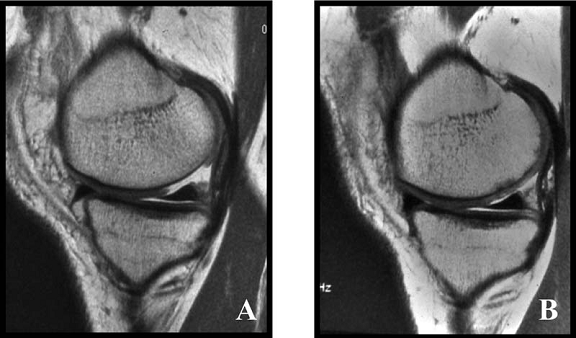

Fig.34. A-scanare inaintea microfracturarii, B-scanare la patru luni dupaa microfracturare.

Evaluarea imaginilor RMN a fost realizata de catre radiologist cu experienta, care cunostea situatia pacientilor si operatia efectuata. Imaginile au fost astfel analizate incat sa se observe zonele cu cartilaj de reparare comparativ cu cel nativ. Repararea morfologica a fost descrisa ca depresiva, neteda, sau mareata comparativ cu cartilajul nativ inconjurator. Volumul de umplere al defectului cu cartilaj reparator a fost masurat folosind imagini sagitale si coronale si a fost gradat ca bun (intre 67% si 100%), moderat (34% la 66%), sau slab (0% la 33%) pe baza procentajului defectului umplut. Interfata cu suprafata cartilajului nativ adiacent a fost evaluata si gradata ca fiind mica ( gaura ≤ 2mm) sau mare (gaura ˃ 2mm). Edemul maduvei osului subcondral a fost gradat ca fiind usor (˂ 1 cm²), moderat (intre 1 si 3 cm²) sau sever (˃ 3 cm²), iar prezenta sau absenta cresterii osoase a fost atent inregistrata.

Imaginile rezonantei magnetice au demonstrat un semnal hiperintens al cartilajului reparator la 22 de pacienti (92%) din cei 24 si usoare edeme subcondrale la 17 pacienti (71%). Umplerea cu cartilajul reparator a fost clasificata ca fiind buna ( 67% la 100%) la majoritatea pacientilor, dar cele mai multe leziuni tratate demonstreaza deprecierea morfologiei cartilajului reparator in cartilaj hialin adiacent. Pentru 6 pacienti au fost disponibile RMN-uri secventiale si toate au demonstrat cel putin un grad de umplere moderat.Nu au existat deteriorari al volumului de umplere la acesti pacienti, dar un pacient a avut o crestere a volumului de umplere in timp. Nu s-a gasit o corelare statistica intre volumul cartilajului reparator si timpul scurs de la microfracturi ( r = 0,173; p = 0,420). Cresterea osoasa a fost demonstrata la sase pacienti (25%). Doua treimi din acestia au avut un grad bun de umplere. Toti cei 13 pacienti cu un bun grad de umplere au avut o imbunatatire a scorului activitatilor zilnice, pe cand doar 3 pacienti cu umplere moderata a defectului si doar unul cu slaba umplere au avut o crestere a acestui scor (p < 0,05). Similar, scorul componentei fizice SF-36 si rata subiectiva a crescut semnificativ la pacientii cu un grad bun de umplere observat in imaginile rezonantei magnetice (p < 0,05). Descresterea scorului functional dupa 24 de luni a fost observata la toti pacientii cu un slab grad de umplere dupa microfracturi, pentru 2 pacienti cu un grad moderat de umplere (p= 0,097) si pentru 3 pacienti cu grad bun de umplere (p < 0,05). Scorul activitatilor zilnice (p < 0,05; r = 0,385) si scorul componentei fizice SF-36 (p ˂ 0,05; r = 0,388) obtinute in timpul rezonantei magnetice demonstreaza o corelatie statistica pozitiva cu gradul de umplere.